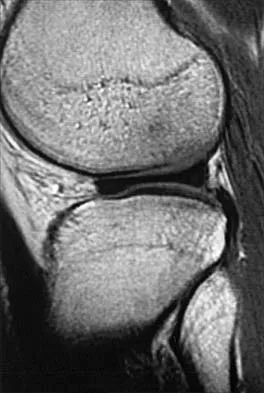

An MRI arthrogram of the elbow is shown in Figure 6. Based on these findings, what is the most likely diagnosis?

Explanation

MRI arthrography is the imaging study of choice for evaluation of medial collateral ligament injuries. Carrino JA, Morrison WB, Zou KH, et al: Noncontrast MR imaging and MR arthrography of the ulnar collateral ligament of the elbow: Prospective evaluation of two-dimensional pulse sequences for detection of complete tears. Skeletal Radiol 2001;30:625-632.